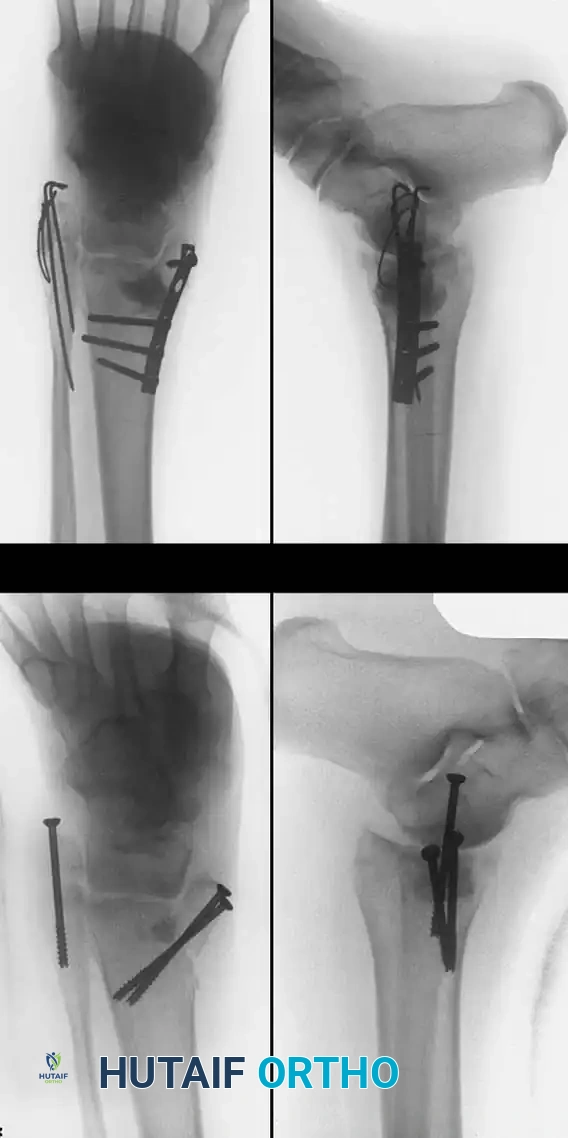

في حالات التشوه من الدرجة الثانية والتي تتضمن التهاب المفصل تحت الكعب مع احتفاظ الكعب بشكله العام، يُنصح بإجراء دمج للمفصل تحت الكعب مع استخدام رقعة عظمية هيكلية. الهدف هنا هو استعادة ارتفاع الكعب ودمج المفصل المتآكل لتخفيف الألم. يتم استخدام نهج جراحي جانبي موسع، ويتم وضع كتلة عظمية مأخوذة من المريض نفسه داخل المفصل لزيادة الارتفاع، مع تثبيت دقيق باستخدام مسامير مجوفة قوية لضمان الانضغاط والالتئام التام.

أما في حالات التشوه من الدرجة الثالثة والتي تتضمن انحرافاً محورياً شديداً، فإن تصحيح المحور يعد شرطاً أساسياً قبل الدمج. قد يتطلب الأمر إجراء قص عظمي لإغلاق الزاوية الجانبية في حالات الانحراف للداخل، أو قص عظمي مع إزاحة وسطية ودوران في حالات الانحراف للخارج. يتم استكمال قص العظم وتعديل المحور قبل وضع مسامير تثبيت دمج المفصل.

تبدأ الجراحة بعمل شق طولي فوق موقع الكسر القديم. يتم استخدام منشار متذبذب لعمل قطع عرضي أو مائل في العظم عند قمة التشوه.

من أهم خطوات الجراحة هي الإزالة الجذرية لجميع الأنسجة الليفية المتندبة بين الشظية والقصبة للسماح بحرية حركة الجزء السفلي من الشظية. بعد ذلك، يتم تثبيت شريحة معدنية قوية على الجزء السفلي من العظم.

يتم استخدام جهاز شد مفصلي دقيق يتم توصيله بالشريحة لسحب الجزء السفلي من الشظية للأسفل وتدويره للداخل بشكل متحكم به، وذلك لاستعادة الطول الطبيعي والمحاذاة الصحيحة للمفصل تحت توجيه الأشعة السينية داخل غرفة العمليات.

بمجرد تحقيق الطول والدوران التشريحي الصحيح، يتم قياس الفجوة العظمية الناتجة عن الإطالة. يتم أخذ رقعة عظمية مطابقة بدقة من عظمة الحوض أو أعلى الساق للمريض، ويتم حشرها في الفجوة.

في الحالات التي تشمل التئاماً خاطئاً في كل من الكعب الداخلي والخارجي، خاصة لدى المرضى الذين يعانون من هشاشة العظام، يتطلب الأمر استراتيجيات تثبيت قوية للغاية. قد يحتاج الكعب الداخلي إلى قص عظمي، وتنظيف الأنسجة الليفية، واستخدام رقع عظمية هيكلية مع شرائح داعمة.